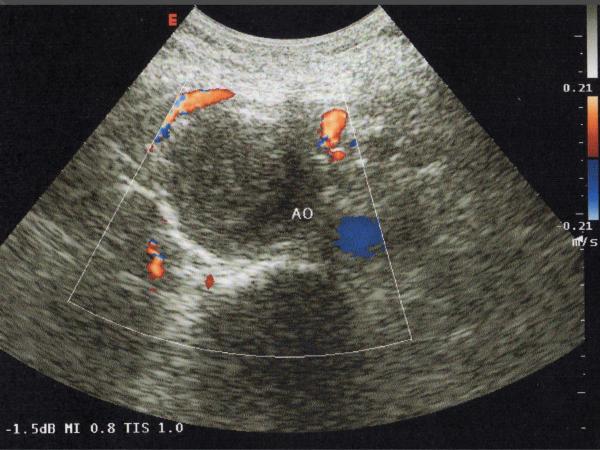

Endovascular repair of anastomotic abdominal aortic aneurysm, after aortobifemoral bypass

Vascular Clinic, Naval and Veterans Hospital of Athens

AVEM2009-Thessaloniki